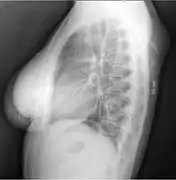

- X-ray of a lipoma

- X-ray showing lipoma